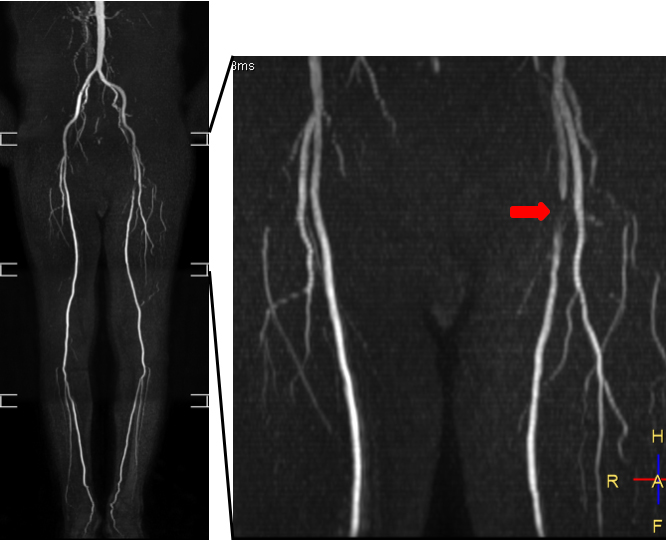

非造影下肢動脈 MRA:造影剤を使用せずに腹部から下肢動脈が描出されており,左浅大腿動脈に狭窄(矢印)を認めます。